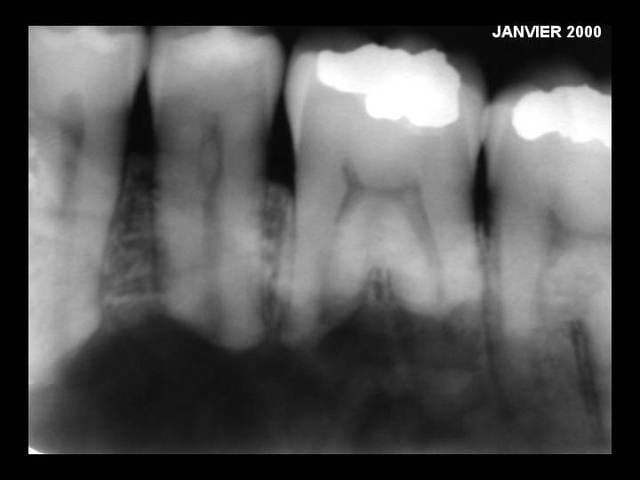

y a deux autres radios que voilà ...

Rx3 jzecpg - Eugenol